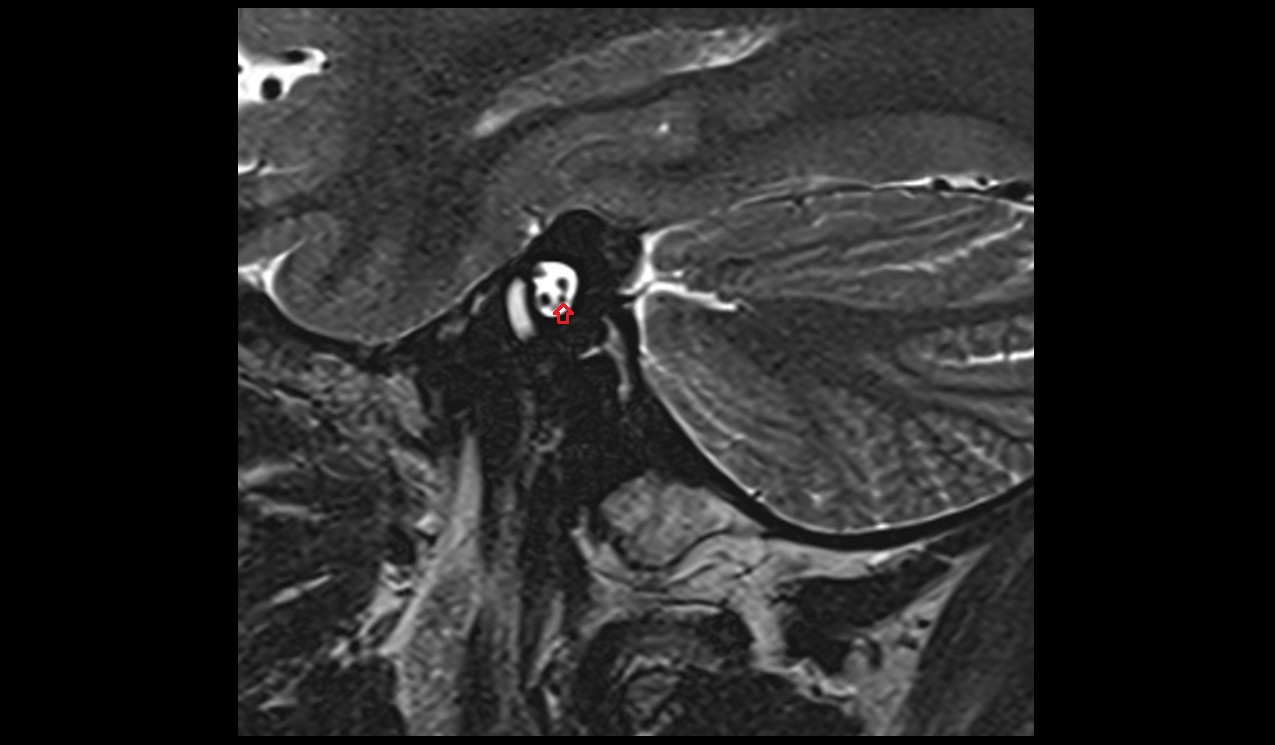

- Cochlear nerve (Cranial nerve VIII)

- Facial Nerve (Cranial nerve VII)

- Semicircular Canals

- Vestibular ganglion

- Vestibule

- Vestibulocochlear nerve (Cranial nerve VIII)